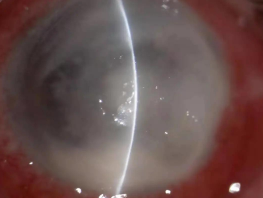

真菌性角膜炎是一種由致病真菌引起的、致盲率極高的感染性角膜病。常見的致病菌為曲霉菌,其次為鐮刀菌、白色念珠菌、頭芽胞菌及鏈絲菌等??沙霈F免疫環(huán)、衛(wèi)星灶、偽足、菌絲苔被、前方積膿及內皮斑。